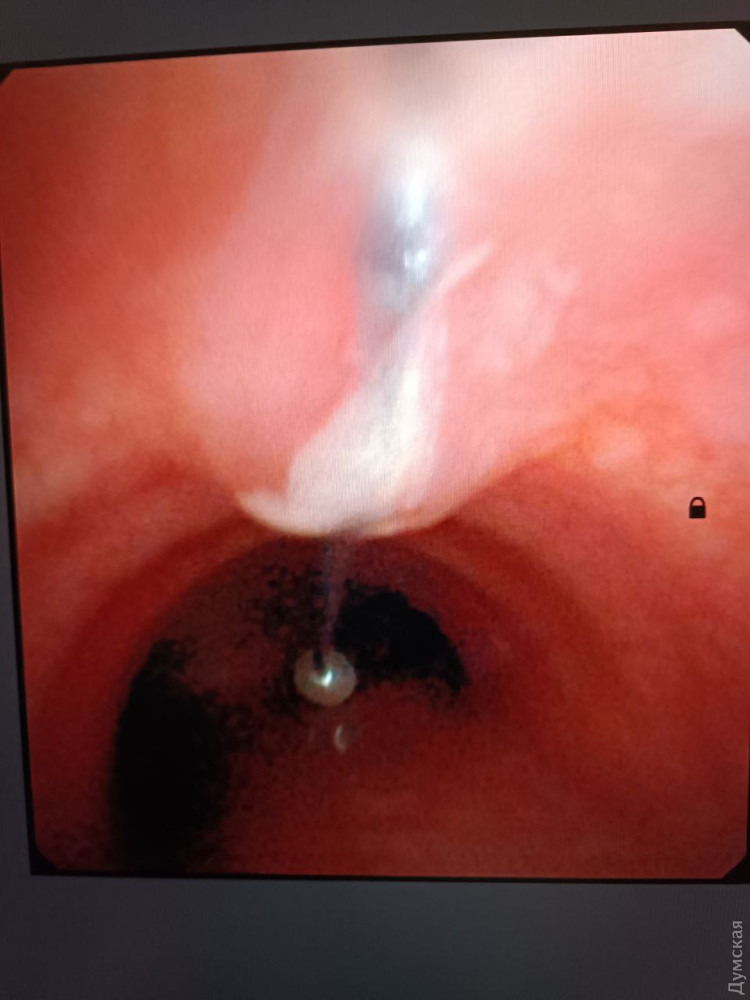

15-річного юнака зі стороннім тілом в трахеї шпиталізували 2 лютого, пише «Бессарабія INFORM». Він випадково «вдихнув» шпильку, яка застрягла на шляху до легень.

У міськлікарні юнаку одразу ж зробили комп’ютерну томографію та з’ясували, що чужорідне тіло застрягло не у стравоході, а саме в трахеї.

Про ювелірну операцію з видалення металевої голки розповів хірург-ендоскопіст Денис Гесслер.

Підлітку під наркозом провели бронхоскопію та дістали чотирисантиметрову голку, яка гострим кінцем встромилася у слизову та нікуди не рухалася. За словами медика, саме завдяки цьому і вдалося запобігти травмуванню.